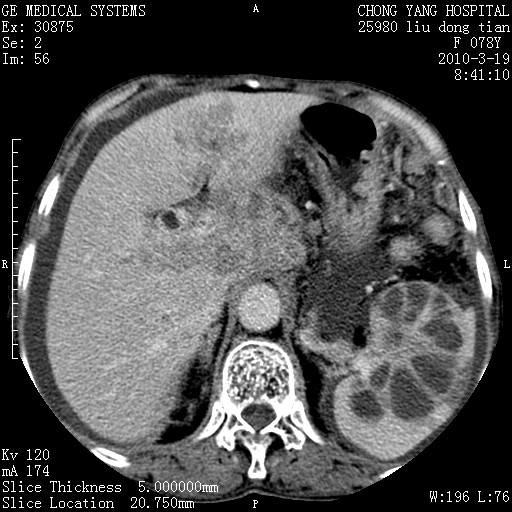

标题: CT25199:F 78Y 腹胀半年 消瘦乏力 [打印本页]

胆囊壁增厚并明显强化,胆囊癌伴多发转移瘤可能性大,淋巴瘤不除外,右肾囊肿,胸腹水.

考虑nhl,肝、脾、腹膜腔及腹膜后多发淋巴结受侵,腹水,右肾囊肿,慢性胆囊炎,右侧少量胸腔积液。

胆囊有软组织影有强化,支持胆囊癌,肝脾、腹膜后淋巴结转移。

nhl的淋巴结多围绕主动脉,而且主动脉会移位,所以不考虑nhl。

分开来讲:肝左叶、尾叶病灶有不均强化像肝癌;

脾脏病灶无强化,像多发囊肿或淋巴管瘤,不除外淋巴瘤(低强化);

胆囊增生性病变:胆囊癌,腺肌增生症,慢性胆囊炎;

肝门、胰腺头、腹膜后多个团块: 淋巴瘤,转移;

腔静脉肝内段细小有无布加可能?

一元论最好了 淋巴瘤所致改变; 胆囊癌转移不像,胆囊周围肝组织清晰,肝癌淋巴结转移?三元论都不止。

最后报的胰头癌多发转移,脾脏单独考虑囊肿或淋巴管瘤。